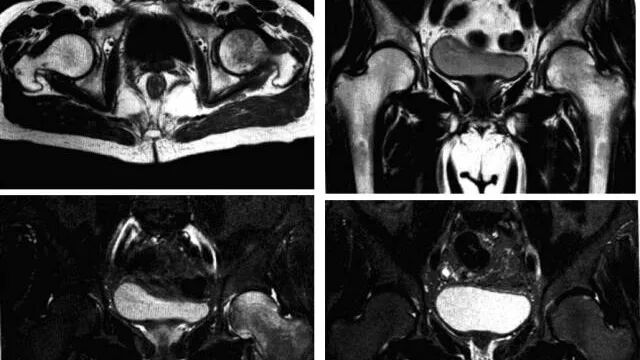

3、MRI:髂关节积液,关节囊肿胀,无股骨头及髋臼破坏征象。(本病诊断*检查手段。)

髋关节一过性骨质疏松

又称髋关节暂时性骨质疏松、暂时性骨髓水肿综合征,是一种病因不明、发病率低的自限性疾病。临床以无外伤史的疼痛为特征并在6-12个月内完全好转为其诊断标准。

病理:骨髓脂肪坏死、骨吸收、骨髓组织周围水肿样变化和轻度纤维化,常伴血管性充血或间质性出血,以及滑膜炎表现,有时可见软骨下骨折,伴有骨痂和肉芽组织,但无骨坏死表现。

临床表现:好发于中年男性或怀孕3个月左右女性,单侧或双侧均可发病,主要症状为无任何诱因出现髋部剧烈疼痛,呈渐进性并放射至膝关节,伴髋关节活动不利、跛行,疼痛加重约在发病后4-8周,并持续一段时间,之后疼痛逐渐减轻至消失,病程约6-12个月,髋部肌肉及股四头肌呈失用性萎缩。实验室检查阴性。

影像诊断:平片及MRI是本病主要诊断手段。

1、平片:活动期表现骨质疏松,股骨头和转子间弥漫性骨密度减低,股骨头软骨下骨皮质吸收,髋臼受累程度轻,无骨侵蚀或破坏,关节间隙保持正常。

2、MRI:骨头至转子间在T1WI低信号,T2WI及脂肪抑制呈均匀一致高信号,无局灶性改变,多伴髋关节积液,周围肌肉层次清晰,随访多于6-10个月内恢复正常,无后遗症。